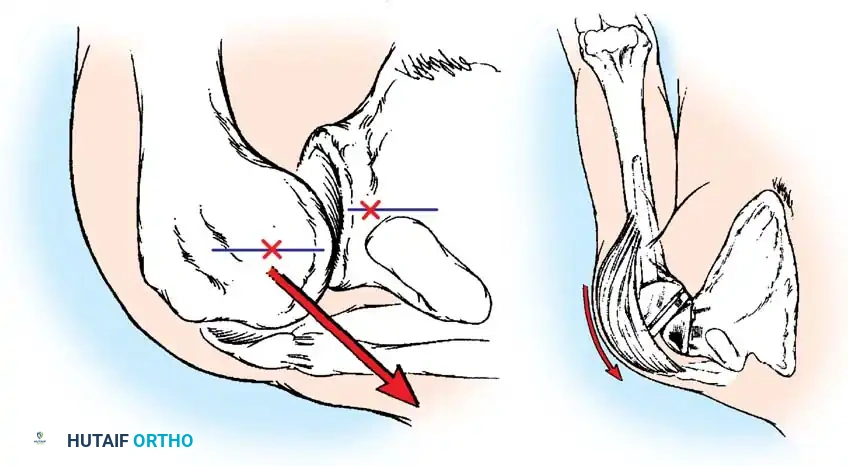

The elbow is a highly constrained, complex hinge joint comprising the ulnohumeral, radiohumeral, and proximal radioulnar articulations. The distal humerus projects anteriorly at an angle of 30 degrees relative to the shaft, and the trochlea is externally rotated 3 to 8 degrees. The normal carrying angle is 10 to 15 degrees of valgus.

- Triceps Management: Several options exist, including a triceps-reflecting approach (Bryan-Morrey), a triceps-splitting approach, or a triceps-sparing approach. The Bryan-Morrey approach involves reflecting the triceps from medial to lateral in continuity with the anconeus and forearm fascia.

The tip of the olecranon is excised to facilitate access to the medullary canal. The distal humerus is prepared by resecting the trochlea and capitellum, preserving the epicondyles if possible to maintain collateral ligament attachments (though less critical in linked designs).